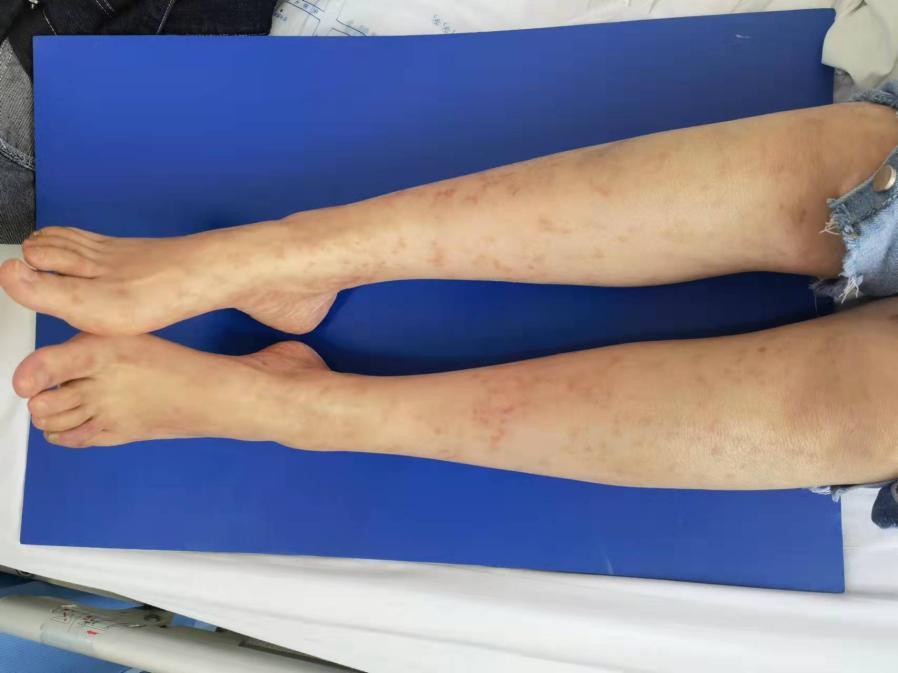

近日,一位30岁的女患者,双腿反复出现网格样青紫,双足趾肿痛、发黑,行走困难,一周前患者上述症状加重,并出现足趾关节肿痛、青紫,行走困难,严重影响日常生活,于是来到西安市红会医院就诊。

为查明患者四肢青斑病因,通过检查患者多种自身抗体、血管炎抗体、狼疮抗凝物等均阴性,于是进一步完善皮肤活检,结果提示“淋巴细胞性血管炎”,随即诊断为“皮肤性血管炎”。医生立即给予患者抗炎、免疫调节、改善循环治疗,患者四肢网状青斑逐渐消退,足趾关节疼痛、黑紫症状明显改善。